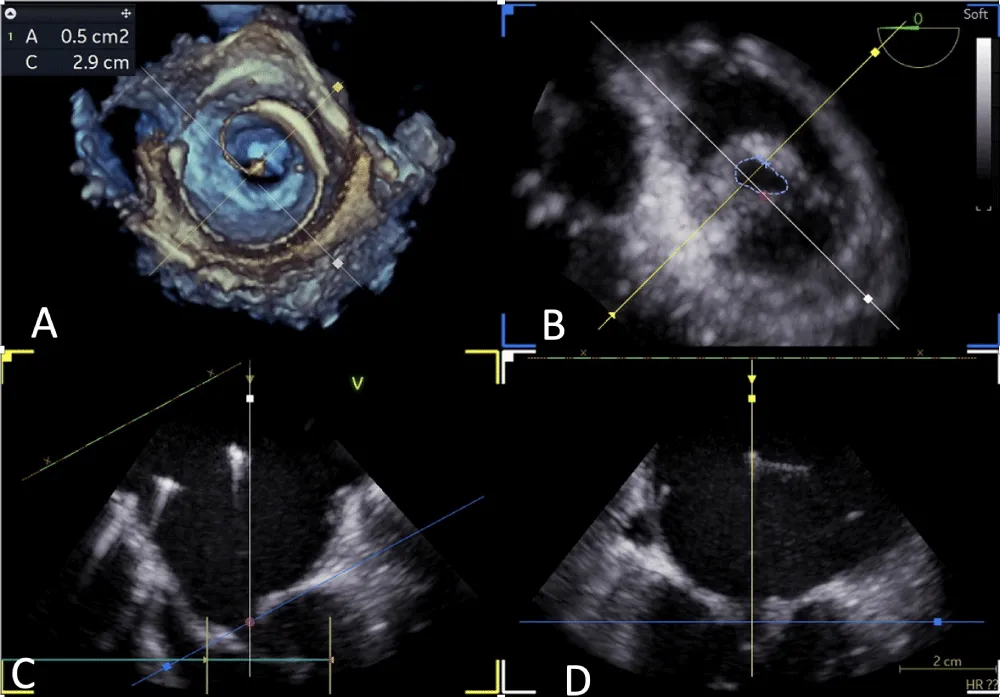

Figure 5: 4Dimensional multiplanar transoesophageal echocardiography – Balloon dilatation of the mitral valve with Inoue balloon.

Download Image

Figure 6: 4Dimensional multiplanar transoesophageal echocardiography – mitral valve after balloon dilatation.

Following a single dilatation, the AV gradient decreased from 82 mm Hg to 30 mm Hg without aortic regurgitation (AR). Subsequently, the mitral valve (MV) was dilated with a 26 mm Inoue balloon (Figures 4,5) (Video 2). After a single dilatation, the MV gradient was reduced from 35/21 mm Hg to 12/5 mm Hg, and the MV area increased from 0.5 cm2 to 1.6 cm2 (Figure 6)

without mitral regurgitation (MR). There were no post-procedural complications.